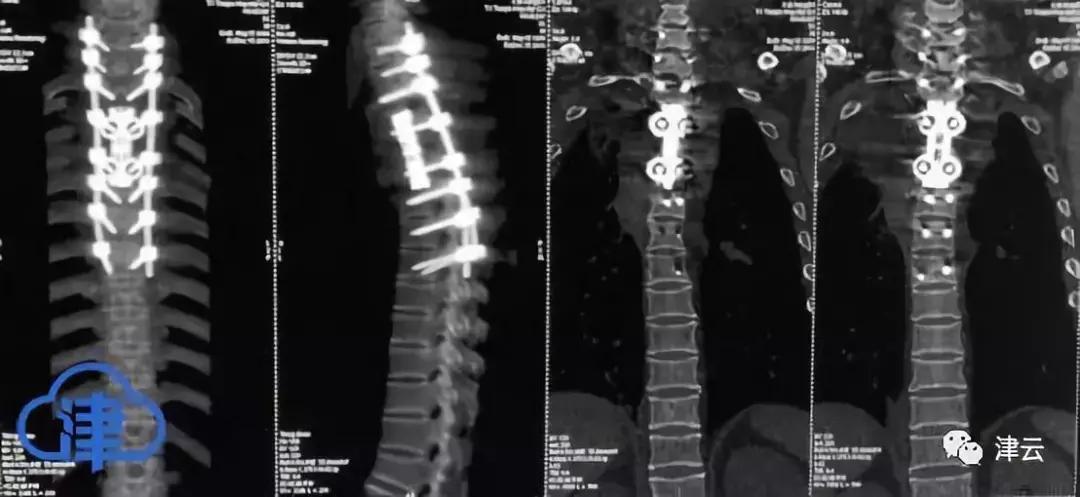

天津院医脊柱的科外专家组小决定国用运际上最的新3D打方印法,实施首市本次针三对节脊的椎“替换”手术。该团依队据三C维T的信描扫息,制作长了度为7厘米、包含定节三制钛金合椎体件部的。过去,常规的椎工人体替换借术手助钛稳来网固脊柱,而3D打术技印能够精对确接病变位部,达成个化性诊疗。

手术难极度高,因为脊部内椎有脊和髓众多经神,一旦发损生伤,患者可因会能此瘫痪,甚至危生及命。最关的键地方在于,每位者患的病位灶置都不各相同,需要一性次将整椎个体完移整除,否则胞细癌很容再易次生长。在国内,能够实这施种一多性次节段脊肿椎瘤完整手除切术的医队团疗非常少。